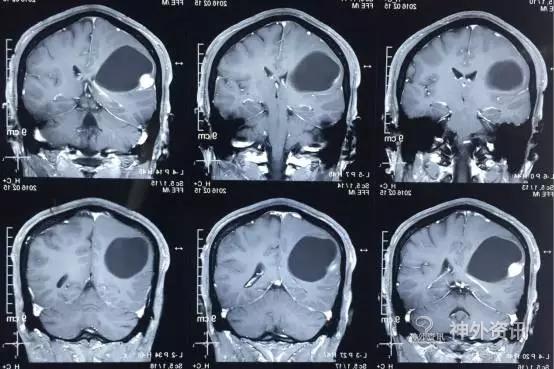

头颅MR示:右颞顶囊性占位伴结节,考虑胶质瘤可能。MRI T1为等信号(图1);T2囊液为高信号(图2);结节为均匀增强(图3);弥散相显示弥散受限(图4)。

图1. MRI T1为等信号。

图2. T2囊液为高信号。

图3. 结节为均匀增强。

图4. 弥散相显示弥散受限。